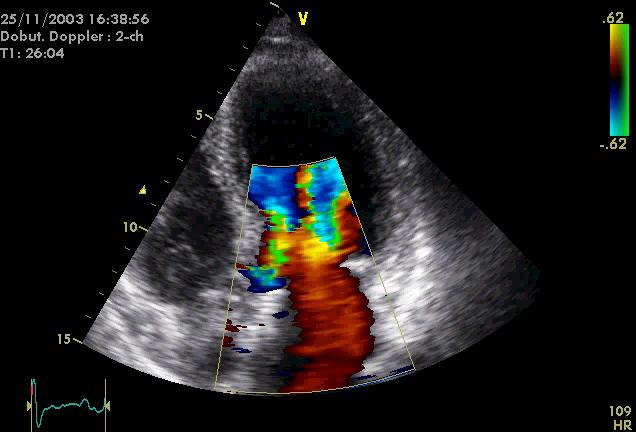

深情注视Narcissus的Echo女神/超声心动图

Echo是希腊神话中的回音女神。她本是一个林中仙女,因天后赫拉嫉妒她的美貌,夺走了她正常说话的能力,只能重复别人的话的最后三个字。后来Echo爱上美少年纳西索斯(Narcissus),却因为只能重复Narcissus的话被他厌恶。Echo羞愧难当,憔悴而死。此后,希腊人便用Echo来表示“回声”。医学中,很多与超声检测相关的仪器都由词根“echo-”构成,如echocardiography(超声心动描记术),echoencephalology(脑回声学)等。